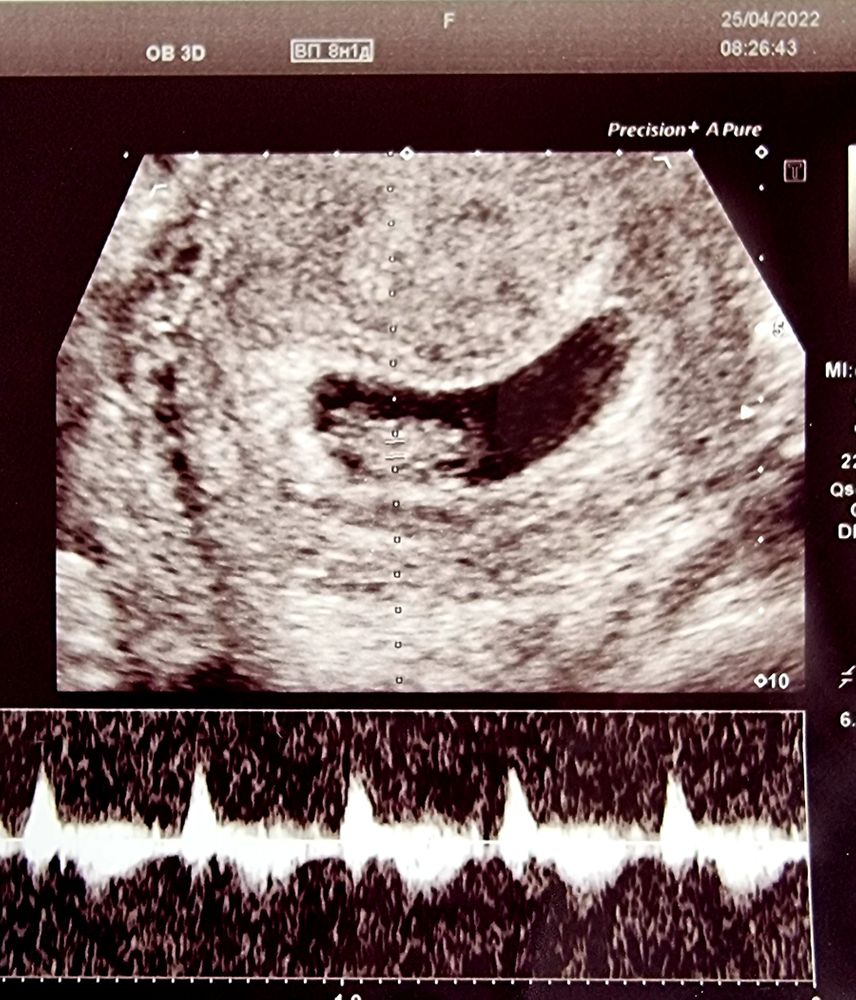

Девочки! Всем привет, была сегодня у врача , сердцебиение плода отличное, срок 6 недель, поставили небольшую угрозу, прописала магний б6 и галакси. Как объяснила , что такая форма плодного яйца, может вызвать выкидыш

Сегодня делала узи вроде тоже форма похожа на ваше узи, однако меня так никто не пугал.

Такая же форма была, это от датчика мне врач объяснила, просто реакция такая . За всю Б ничего кроме витаминов не принимала

наташка, мне врач объяснил, что если «бобовое »предлежание плодного яйца, то это угроза . Вам не ставили угрозу?